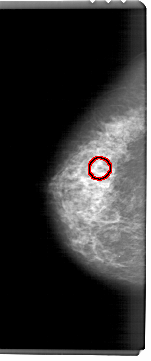

A_1461_1.RIGHT_MLO

RIGHT_CC LINES 5326 PIXELS_PER_LINE 2491 BITS_PER_PIXEL 12 RESOLUTION 43.5 NON_OVERLAY

FILE: A_1461_1.LEFT_MLO.OVERLAY

TOTAL_ABNORMALITIES 1

ABNORMALITY 1

LESION_TYPE CALCIFICATION TYPE AMORPHOUS DISTRIBUTION CLUSTERED

ASSESSMENT 4

SUBTLETY 4

PATHOLOGY BENIGN

TOTAL_OUTLINES 1